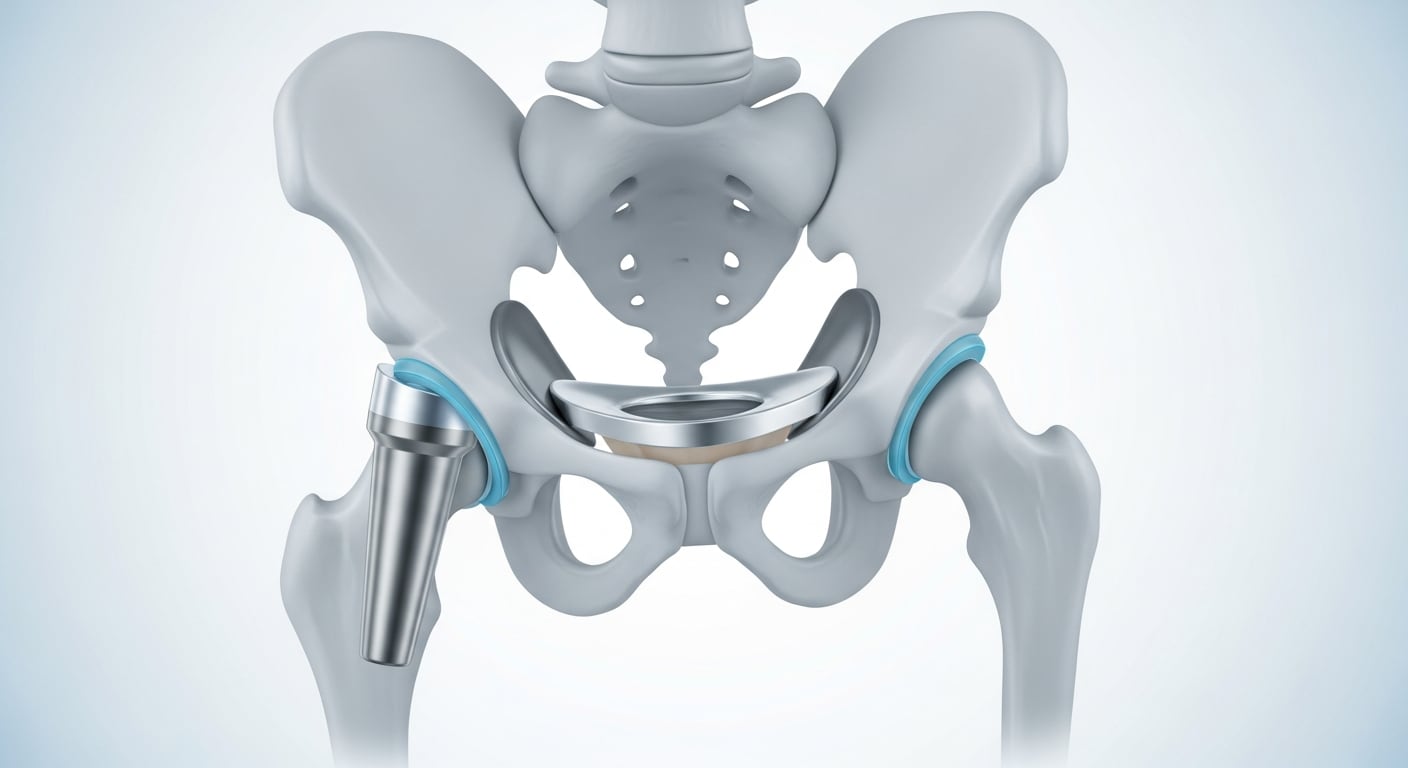

El número de personas que presentan lesiones de cadera y requieren prótesis continúa en aumento tanto en adultos mayores como en jóvenes, impulsado por el incremento de la esperanza de vida y la popularidad de actividades deportivas de alto impacto.

Este fenómeno responde al envejecimiento poblacional y a la mayor exposición a factores de riesgo en todas las edades. Los avances en técnicas quirúrgicas y en la durabilidad de las prótesis, que superan los 20 años, han elevado la relevancia de la prevención y la identificación temprana de los síntomas. Actualmente, la cirugía de cadera es una de las intervenciones más solicitadas en traumatología.

Los tratamientos disponibles varían desde el reposo y la fisioterapia hasta la implantación de prótesis de larga duración, permitiendo una recuperación personalizada gracias a los avances en cirugía ortopédica.

Opciones de tratamiento y avances en prótesis de cadera

En los casos graves o cuando existe un proceso degenerativo avanzado, la implantación de una prótesis de cadera es la opción más indicada. Esta intervención se recomienda cuando la calidad de vida del paciente está gravemente limitada y las opciones conservadoras han dejado de ser efectivas. Determinadas fracturas, especialmente las que afectan la cabeza femoral, requieren este procedimiento quirúrgico.

De acuerdo con la American Academy of Orthopaedic Surgeons (AAOS), la cirugía de reemplazo de cadera es una de las más seguras y eficaces en ortopedia.

Algunos centros de salud han implementado intervenciones de cirugía ambulatoria, lo que permite que el paciente regrese a casa el mismo día, siempre que no existan enfermedades adicionales y que cuente con apoyo adecuado en el hogar. La adaptación de los protocolos y la selección del implante más apropiado favorecen una recuperación personalizada y más rápida.

Las prótesis modernas de cadera superan los 20 años de duración, una mejora significativa respecto a los reemplazos que debían realizarse cada diez años. El control del dolor postoperatorio y la rigurosa selección de los candidatos han facilitado estos avances, según la AAOS.